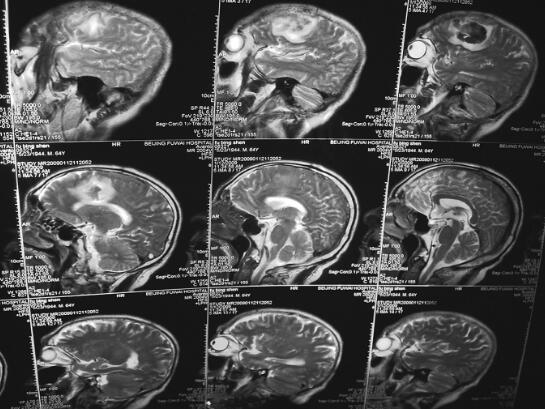

诊治经过:患者入院后仍发热,体温37.8~39.2℃,意识淡漠,嗜睡状态,1月5日行脑CT示右侧额叶脑白质内小片状低密度影。1月12日MRI示颅内多发病灶,不除外颅内额叶血肿合并颅内多发感染灶(图2、图3),行3次血培养均为金黄色葡萄球菌,给予利奈唑胺0.6g,ivgtt,每12小时1次及左氧氟沙星0.2g,ivgtt,每日2次静点治疗,并同时给予营养支持及对症治疗,约1周后患者体温逐渐降至正常,体温正常后继续给予利奈唑胺静点治疗4周,患者未再发热,二尖瓣为中量反流,心脏不大,可暂不予手术治疗,继续随访。

图2 2009年1月12日入院时,头颅MRI示颅内多发病灶

图3 2009年1月12日入院时,头颅MRI示颅内多发病灶